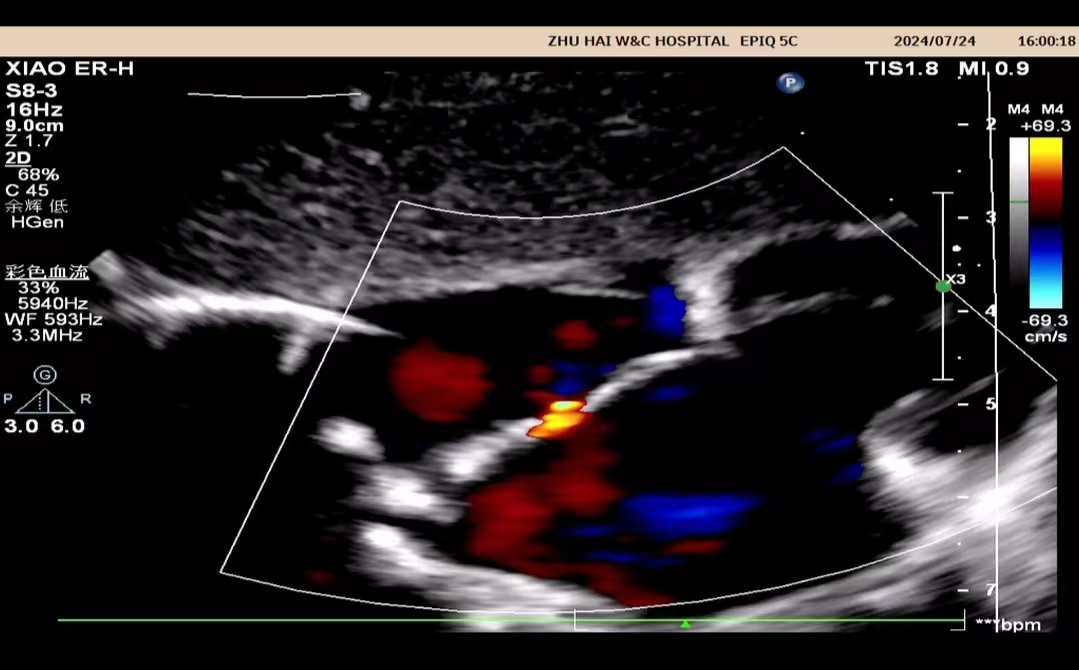

心脏彩超是能够动态显示心腔内部结构、心脏搏动和血液流动情况的一种无创性检查技术。通俗地说,心脏探头有点类似于摄像机的镜头,通过镜头的不断移动和变换,让心脏的各个结构得到准确的呈现,从而让医生能够根据这些图像判断心脏是否存在问题。

大部分都可以通过心脏彩超查出,例如:房间隔缺损,室间隔缺损,动脉导管未闭,心内膜垫缺损,法洛四联征、大动脉转位等。

心脏彩超除了对于先天性心脏病有比较好的显示效果外,对于后天因素所导致的心脏病,同样能够有很好的诊断效果。比如常见的瓣膜狭窄、瓣膜关闭不全、风湿性心脏瓣膜病、冠心病、肥厚型心肌病、扩张性心脏病等。